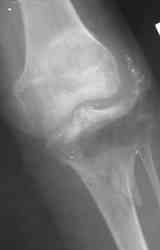

Уважаемые коллеги! На консультацию обратилась женщина, 23 года. В феврале огнестрельное ранение колена. Снимки первичные и майские в приложении. А также внешний вид раны. Укорочения конечности нет. Разгибание в коленном суставе отсутствует. Сгибание сохранено. Нестабильности нет.Дно раны - мертвая кость.

по снимкам у пациентки на данный момент сохраняется дефект наружного мыщелка б\б кости, который со временем приведет к вальгусной дефеормации голени и в настоящий момент практически отсутствует бугристость б\б кости, т.е. зона прикрепления собвственной связки, которую можно в принципе выкроить из средней порции сухожилия 4-хглавой со средней частью надколенника, но сначала необходимо запонить дефект костной ткани, либо путем свободной кости пластики, либо формированием отщепа б\б кости с микродистракцией в КДА Илизарова. т